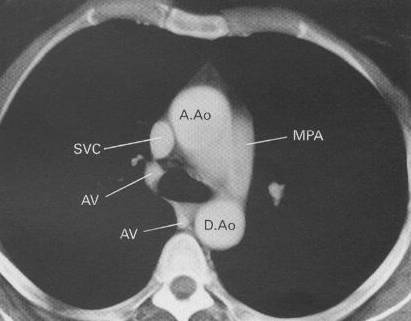

key structures on CT in the mediastinum:

CT of normal mediastinum. Five 1-cm thick sections have been selected to show the

important anatomical features (AE). The level of each section is illustrated in the

diagram. A.Ao = ascending aorta, AV = azygos vein, D.Ao = descending aorta, IA =

innominate artery, LCA = left carotid artery, LIV = left innominate vein, LPA = left

pulmonary artery, LSA = left subclavian artery, MPA = main pulmonary artery, Oes =

oesophagus, RIV = right innominate vein, RPA = right pulmonary artery, SVC = superior vena

cava, T = trachea, RA = right atrium, LA = left atrium, RVO = right ventricular outflow

tract.